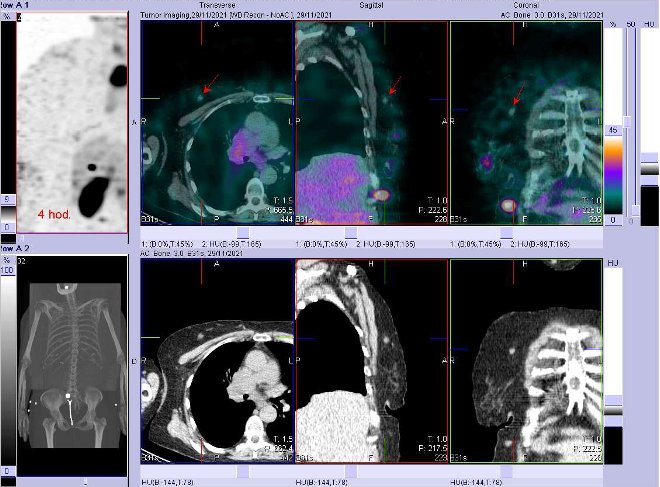

/ Obr. č.

2: Celotělová scintigrafie v přední a zadní projekci a fúze SPECT/CT 4 hod. po aplikaci OctreoScanu. Zaměřeno na ložisko v mediastinu.

/ Obr. č. 4: Fúze obrazů SPECT a CT. Zaměřeno na ložisko v mediastinu. Vyšetření 4 hod. po aplikaci OctreoScanu.

Závěr: mnohočetná patologická ložiska se zvýšenou denzitou somatostatinových receptorů – největší a nejnápadnější je v mediastinu vpravo velikosti cca 4,5x4,5x4,8 cm, dále v pravém plicním hilu, pravém laloku štítné žlázy, zřejmě v uzlině v blízkosti pankreatu, mnohočetná podkožní ložiska na hrudníku, břiše, na zádech, ve zvětšené pravé nadledvině, v pánvi vlevo za psoatem, susp. v pravém jaterním laloku. Drobné ložisko v pravém prsu je patrné na ldCT, akumulace radiofarmaka jen nepatrná. Nález svědčí pro mnohočetné metastázy NET. Primární tumor v mediastinu? v plicích? jinde?